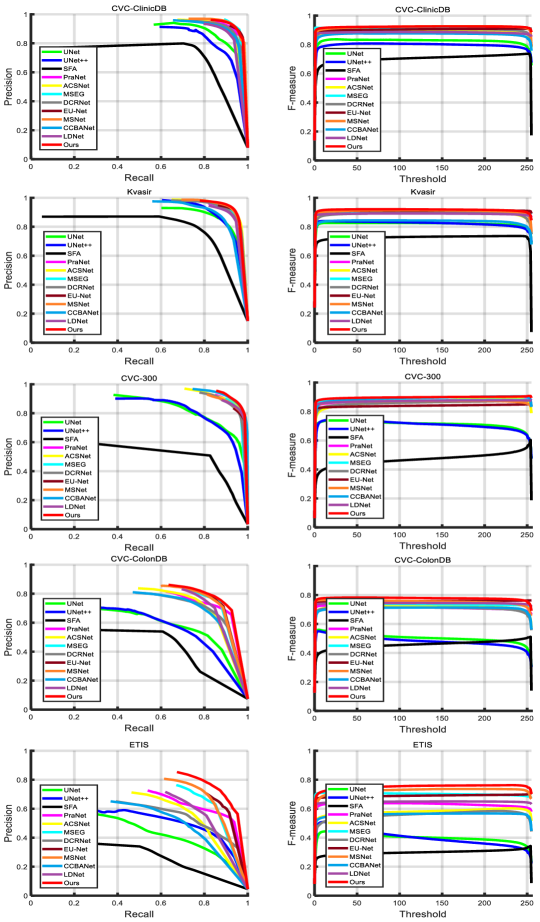

Furthermore, we present precision-recall and F-measure curves in Fig. 6. As shown Fig. 6, it can be seen that our segmentation model achieves much better results compared to other state-of-the-art polyp segmentation methods. Thus, the results further validate the effectiveness of the proposed polyp segmentation method.